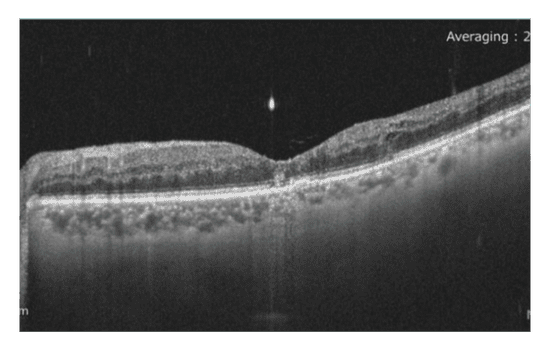

Following administration of a third anti-VEGF injection, the patient’s BCVA improved to 20/20. Additionally, retinal appearance showed signs of improvement, and the previously observed edema had resolved. To further assess retinal function, a repeat ERG was conducted, after one month and on the day of the first PRP session, revealing promising results. The implicit time decreased from 35.5 to 33.9 ms, indicating a positive response to treatment, albeit with residual ischemia. Moreover, there was a 50% recovery in amplitude (from 11.7 µV to 20.8 µV), suggesting enhanced retinal functioning after three injections and directly before laser treatment.